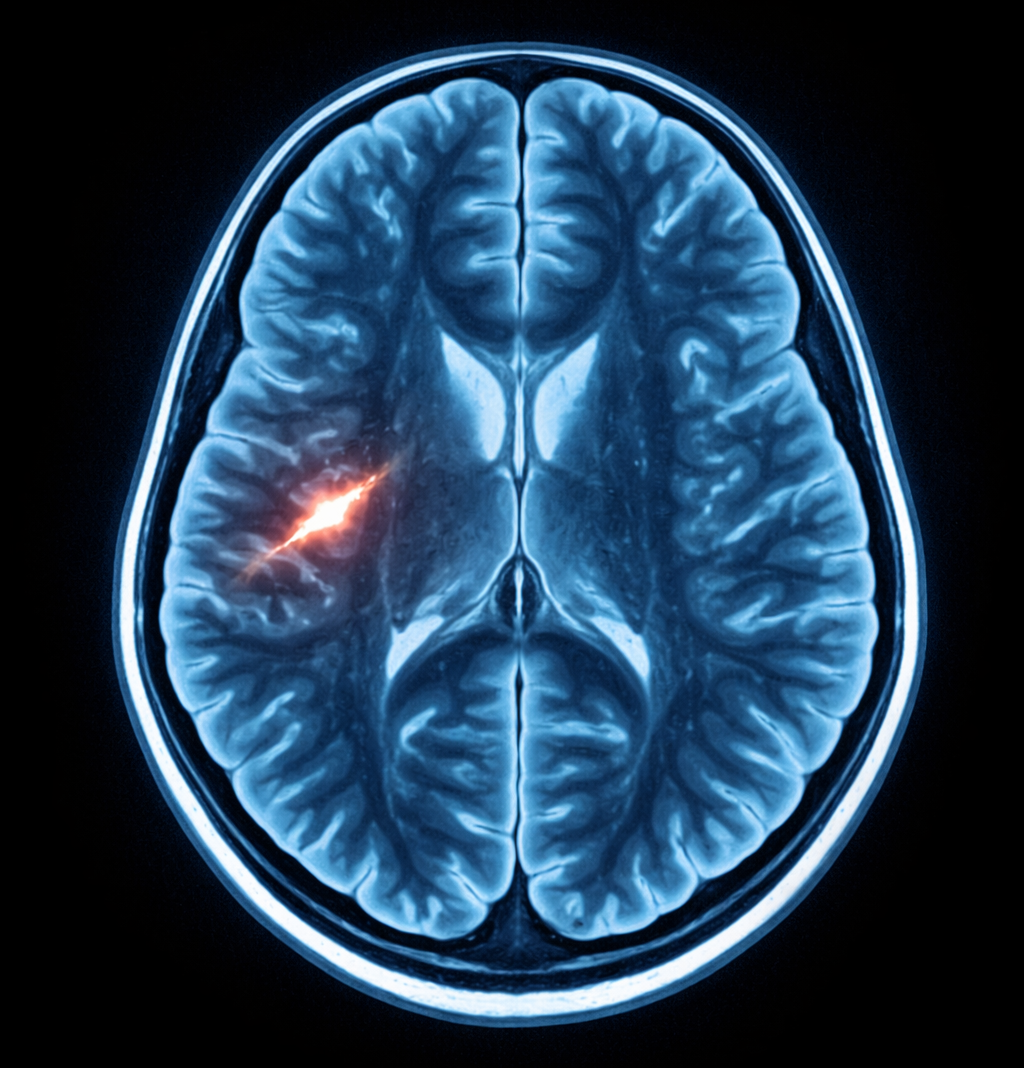

Pourtant, une étude scientifique internationale de grande ampleur, publiée dans la revue Proceedings of the National Academy of Sciences (PNAS) et fondée sur l’analyse de 7 876 IRM dans 29 pays, suggère une réalité plus lourde : les inégalités femmes-hommes ne sont pas uniquement une injustice sociale. Elles peuvent aussi s’associer à des différences structurelles mesurables dans le cerveau, avec un fil conducteur central : le stress chronique.

Les chercheurs ont mené une méta-analyse portant sur 7 876 IRM issues de 29 pays, réparties en 139 échantillons, comprenant 4 078 femmes et 3 798 hommes.

L’objectif était de mesurer des différences de structure cérébrale entre femmes et hommes, puis d’évaluer si ces écarts variaient selon l’inégalité femmes-hommes à l’échelle des pays.

Le travail scientifique se concentre sur un indicateur : l’épaisseur corticale (cortical thickness), un marqueur de structure cérébrale fréquemment utilisé en neurosciences.

Ce marqueur n’est pas un détail : il est souvent mobilisé pour comprendre comment certaines expositions (stress, adversité, conditions de vie défavorables) peuvent être associées à des variations dans le cerveau.

L’étude observe une tendance : dans plusieurs régions cérébrales, les différences entre femmes et hommes varient selon le niveau d’inégalité de genre.

Dans les pays plus égalitaires, ces régions présentent peu de différences structurelles, ou parfois une épaisseur corticale plus importante chez les femmes.

Dans les pays plus inégalitaires, l’épaisseur corticale est relativement plus faible chez les femmes par rapport aux hommes.

Les principales régions identifiées incluent :

- le cortex cingulaire antérieur (right caudal anterior cingulate)

- le cortex orbitofrontal médian (right medial orbitofrontal)

- le cortex occipital latéral (left lateral occipital cortex)

Ces zones sont souvent associées à des fonctions impliquant la régulation émotionnelle, le traitement du stress, et certains mécanismes liés à la vulnérabilité psychique.

L’intérêt de cette étude n’est pas d’affirmer que le cerveau des femmes serait “naturellement” différent ou inférieur. Au contraire, elle soulève l’hypothèse inverse : l’environnement social, lorsqu’il est défavorable, peut contribuer à produire des effets mesurables.

Dans les reprises médiatiques de cette recherche, le psychiatre Nicolas Crossley évoque l’idée que l’inégalité pourrait laisser une marque durable, comme une forme de “cicatrice” (scar) sur le cerveau.

Ce qui frappe, c’est la cohérence du raisonnement : l’inégalité devient une variable environnementale, répétitive, et potentiellement toxique, au même titre que d’autres formes de stress chronique.

Cette étude ne prouve pas que le cerveau des femmes est biologiquement inférieur, ni que toutes les femmes seraient affectées de la même manière.

Elle met en évidence une association entre inégalités de genre à l’échelle des pays et différences structurelles observées, et elle ouvre une hypothèse : des environnements plus défavorables aux femmes pourraient contribuer à ces variations, via le stress chronique et d’autres facteurs sociaux.

Une étude publiée dans PNAS en 2023, basée sur 7 876 IRM dans 29 pays, associe l’inégalité femmes-hommes à des différences structurelles dans certaines régions du cerveau chez les femmes.